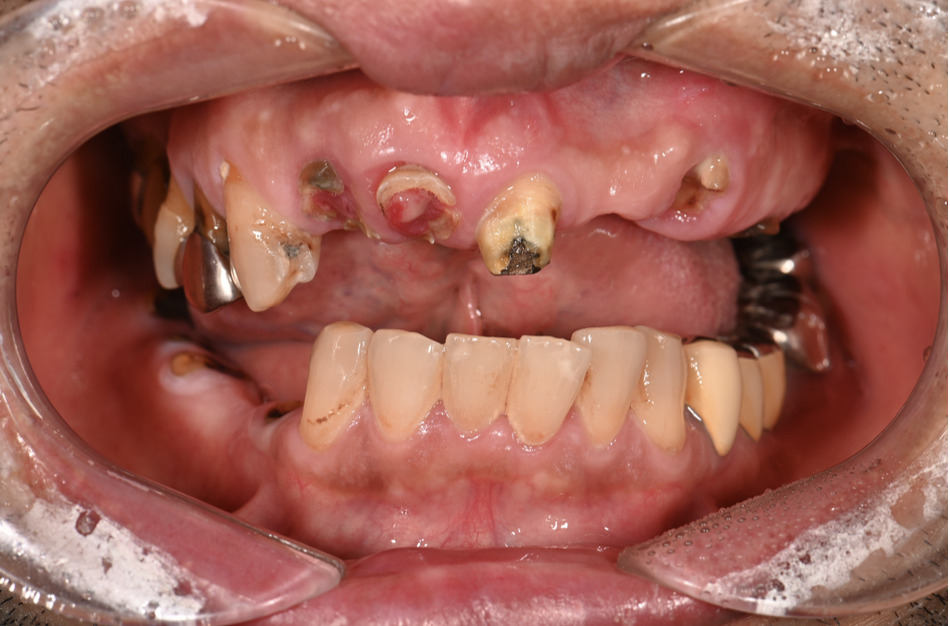

| 主訴 | 歯がグラグラして噛めない |

|---|---|

| 治療内容 | 上顎、下顎に対するインプラント治療 |

| 治療期間 | 1日 |

| 治療費 | 409万2千円 |

| 治療 リスク | 最終的な歯が入るまでは仮歯になります。 |